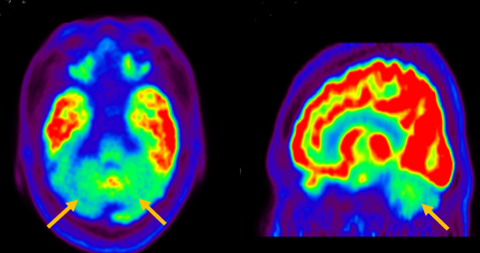

루이소체 치매는 파킨슨 증상 발생 초기나 그 이전부터 빠르게 진행되는 인지 기능 저하가 동반되는 질병입니다. 퇴행성 치매의 원인 중 두 번째로 많습니다. 반복되는 환시 증상과 인지, 의식 및 집중력의 변동이 특징적으로 나타납니다. 뇌 자기공명영상(MRI)에서 전반적인 대뇌 위축이 나타나며, 알츠하이머병에 비해 상대적으로 후두엽, 내측 측두엽이 보존되는 모습이 관찰됩니다. 뇌포도당 양전자 단층촬영(PET)을 시행하면 쐐기소엽(cuneus) 및 쐐기앞소엽(precuneus)의 대사가 감소한 상태가 확인됩니다. 그러나 뒤띠이랑(posterior cingulate gyrus)은 상대적으로 보존된 모습을 볼 수 있습니다.

[루이소체치매 환자의 뇌포도당 양전자 단층촬영에서 확인되는 비대칭적인 대사 기능 저하]